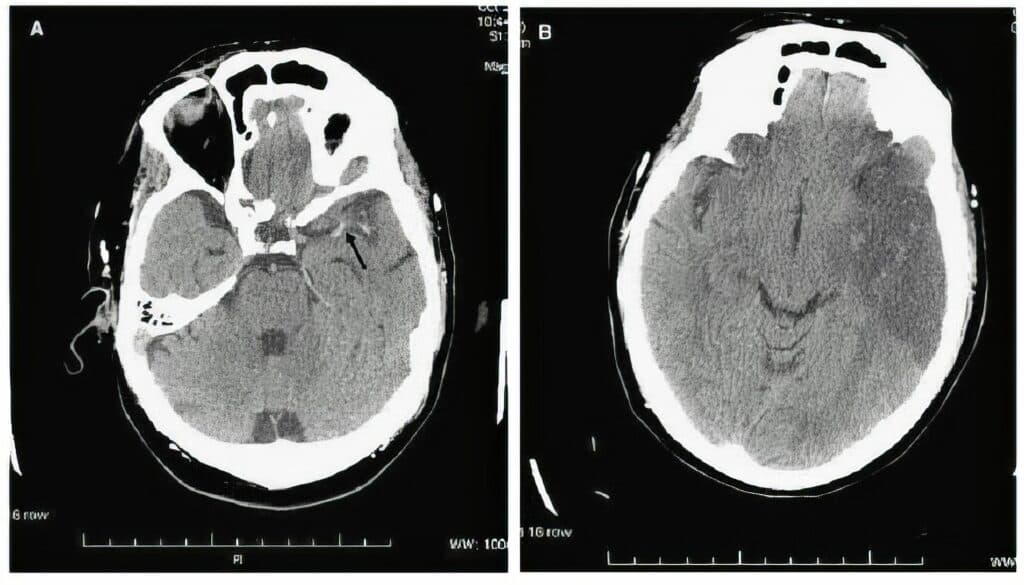

El ictus, una de las principales emergencias médicas y la segunda causa de muerte en España, se produce por la interrupción del flujo sanguíneo en el cerebro, provocando una alteración brusca de la función neurológica. En 2024, el 75 por ciento de los ictus registrados en Canarias fueron de tipo isquémico (2.020 casos), mientras que el 25 por ciento restante fueron hemorrágicos (658 casos). En cuanto a la distribución por sexo, los ictus isquémicos afectaron a 1.197 hombres y 823 mujeres, y los hemorrágicos a 357 hombres y 301 mujeres.